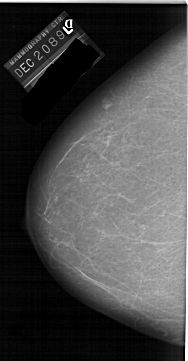

A_1159_1.LEFT_CC

LEFT_CC LINES 6496 PIXELS_PER_LINE 3376 BITS_PER_PIXEL 12 RESOLUTION 43.5 NON_OVERLAY